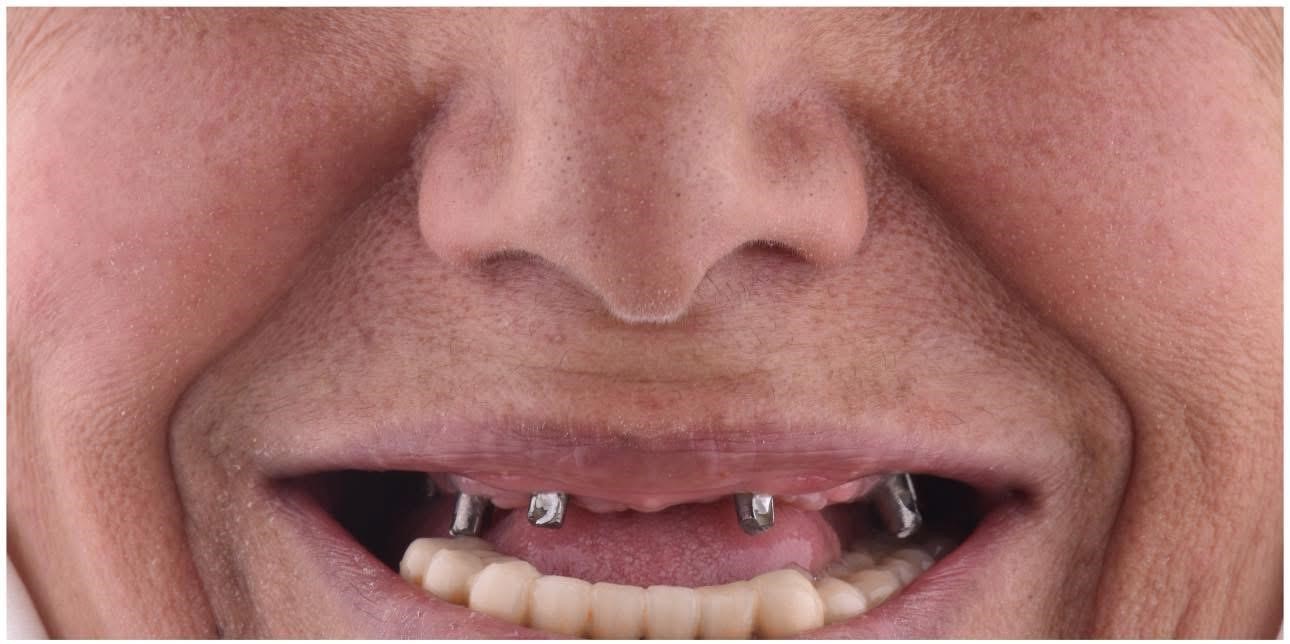

Our Work